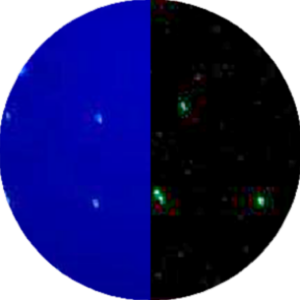

Live/dead/apoptotic cells